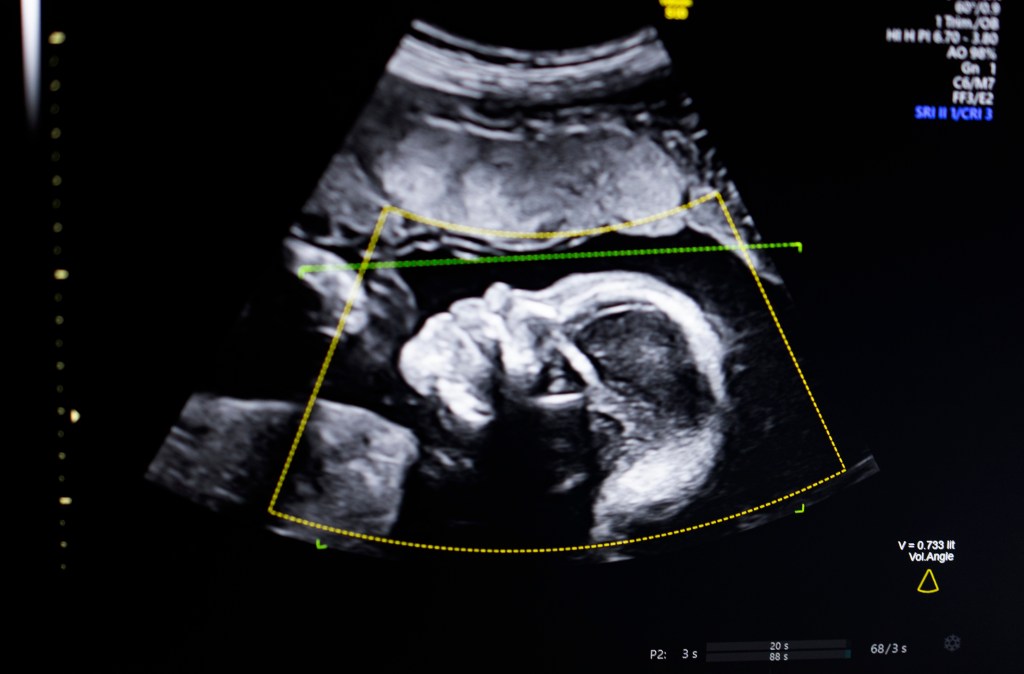

BioticsAI, the victor of TechCrunch Disrupt’s Startup Battlefield in 2023, has achieved a significant milestone by obtaining FDA clearance for its innovative AI-driven software designed to detect fetal abnormalities in ultrasound images. This development marks a pivotal advancement in prenatal care, aiming to enhance diagnostic accuracy and improve maternal and fetal health outcomes.

BioticsAI’s platform leverages advanced computer vision AI to enhance the quality and accuracy of fetal ultrasound assessments. The software offers several key functionalities:

– Quality Assessment: Ensures that ultrasound images meet high standards, reducing the likelihood of misdiagnosis due to poor image quality.

– Anatomical Completeness: Verifies that all necessary anatomical structures are captured, providing a comprehensive view of fetal development.

Bustami emphasized the transformative potential of this technology, stating that prenatal ultrasounds are fundamental in monitoring pregnancies. However, the variability in image quality can lead to diagnostic errors. By implementing AI-driven assessments, BioticsAI aims to mitigate these risks and enhance diagnostic precision.

The integration of AI into prenatal diagnostics represents a significant leap forward in maternal-fetal medicine. Traditional ultrasound assessments are highly dependent on the skill and experience of the operator, leading to variability in diagnostic accuracy. By standardizing assessments through AI, BioticsAI’s software has the potential to:

– Enhance Early Detection: Identify fetal abnormalities at earlier stages, allowing for timely interventions and management strategies.